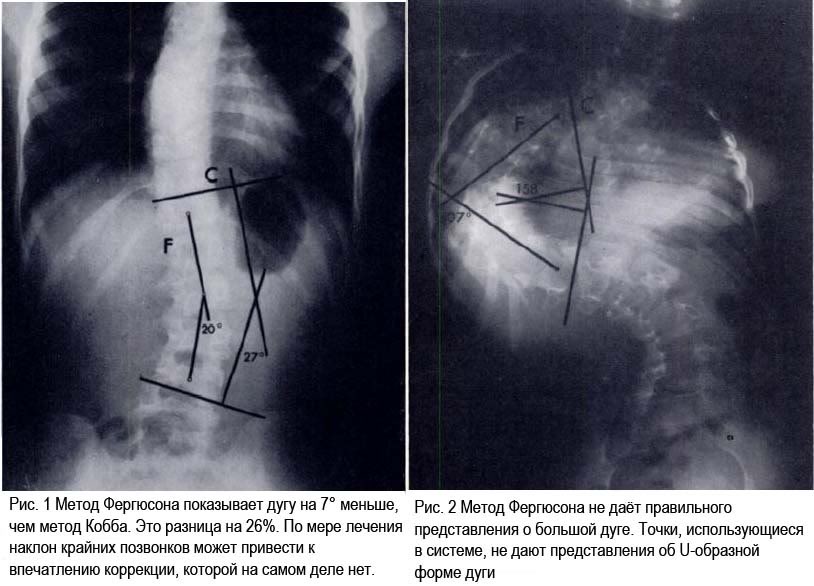

Метод Фергюсона, сравнение методов Кобба и Фергюсона

Метод Фергюсона не даёт аккуратного измерения дуг более 50°, метод Кобба метод не даёт аккуратного измерения дуг до 50°. Т.о., метод Фергюсона должен быть использован для измерения сколиозов до 50°, метод Кобба должен быть использован для измерения сколиозов более 50°.

Метод Кобба не измеряет само искривление, он измеряет угол наклона крайних поверхностей крайних позвонков. Крайние позвонки могут быть наклонены сами по себе, без значительного влияния на дугу, таким образом искажая картину.

Метод Фергюсона представляет саму дугу и наклон крайних позвонков не влияет на показатели. Очень часто велик соблазн использовать метод Кобба, потому что он даёт иллюзию достижения блольшей корекции в процессе лечения.